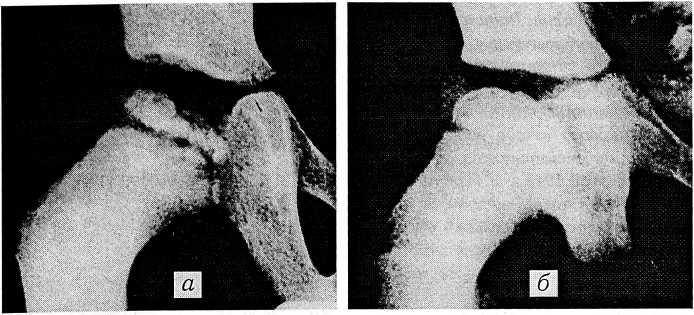

Рис. 2. Плечелопаточный периартрит: а — до лечения (tendinitis calcarea); б — после 20 процедур магнитотерапии.

По поводу плечелопаточного периартрита магнитотерапия проведена 286 пациентам. В эту группу включены только больные, у которых на рентгенограммах плечевых суставов был обнаружен tendinitis calcarea (рис. 2). Результаты лечения оценивались по четырехбалльной системе. Выздоровление (отсутствие болезненности, полный объем активных движений в плечевом суставе, отсутствие тени патологического очага на контрольной рентгенограмме) констатировано у 143 (50%) человек; значительное улучшение (легкая болезненность при резких движениях, не нарушающая трудоспособности, тень рассасывающегося очага на контрольной рентгенограмме) — у 89 (31,1%); улучшение (уменьшение болезненности, увеличение объема движений, признаки рассасывающегося очага на рентгенограмме) — у 36 (12,6%); состояние без изменений — у 18 (6,3%).